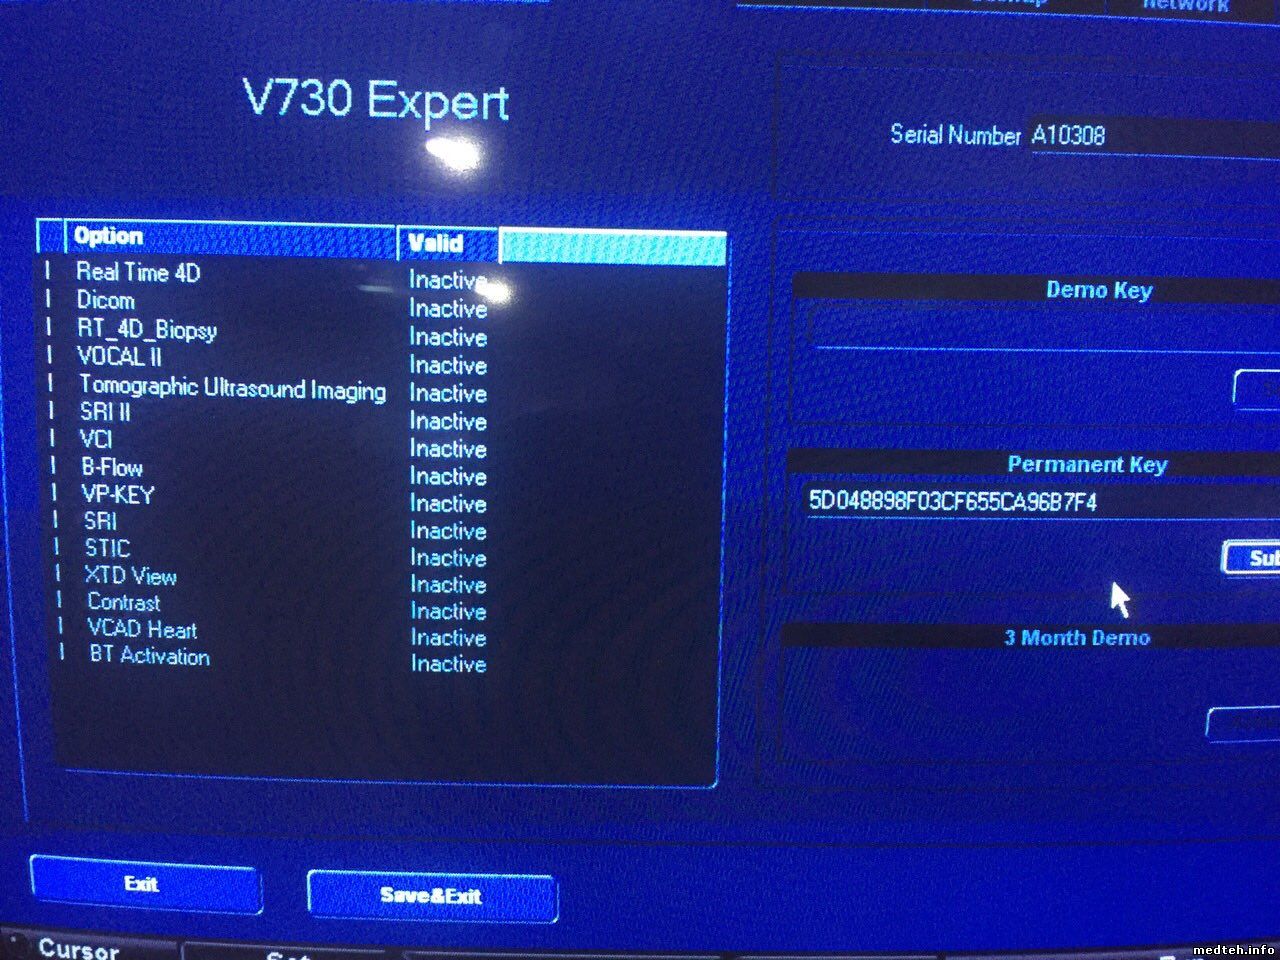

Медицинская Техника: УЗИ с Ge Voluson 730 Expert